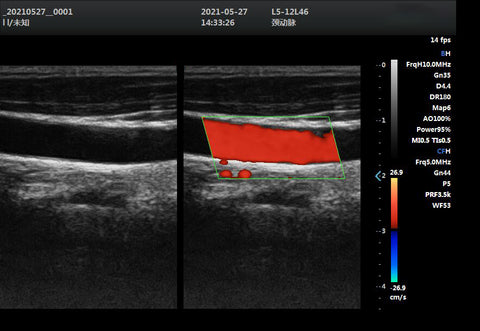

• Linear transducers: These have a linear arrangement of piezoelectric crystals that produce a rectangular beam of sound waves. They are used for imaging superficial structures, such as blood vessels, thyroid, breast, and tendons. They have a high frequency and a good resolution in the near field, but a poor resolution in the far field.